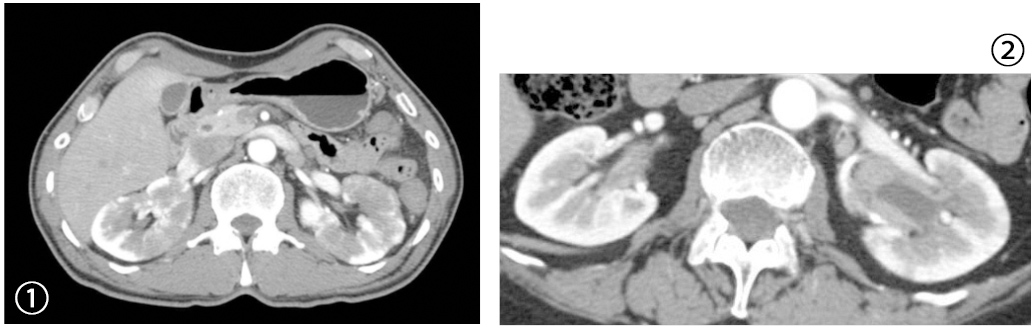

IgG4関連腎臓病の特徴的画像所見。

①腎実質の多発性造影不良域、②腎盂の病変